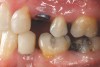

Fig 11. Corticotomy SFOT. A 42-year-old male presented with a history of extraction orthodontic therapy.

Figure 11

Fig 12 (and Fig 13). Incisors were too upright and had severe incisal wear. He was concerned about esthetics of the worn teeth and his insufficient lip support. Progress photo and panorex 9 months after corticotomies were performed on Nos. 6 through 11. Previous extraction sites were reopened orthodontically to improve function and fill lip support. Incisal edges were restored provisionally with composite resin. Note that despite the creation of adequate spaces to replace missing teeth, there is inadequate room for placement of dental implants because of severe tipping of all the anterior teeth. Osteotomy SFOT may have been a better choice because it would have allowed needed alveoloskeletal correction (without excessive tipping) instead of the primarily dentoalveolar correction common in corticotomy SFOT. Restorative dentist: Brad Jones, DDS.

Figure 12

Fig 13 (and Fig 12). Incisors were too upright and had severe incisal wear. He was concerned about esthetics of the worn teeth and his insufficient lip support. Progress photo and panorex 9 months after corticotomies were performed on Nos. 6 through 11.

Figure 13